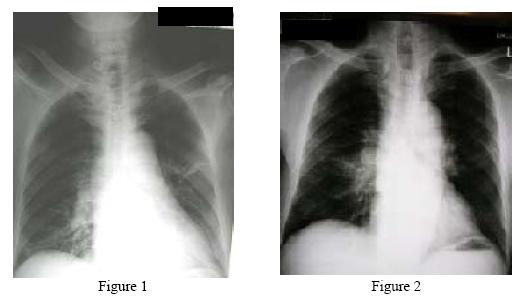

He was admitted in 2/2005 for chest infection, with fever for 1 day, cough with scanty sputum. Physical examination was unremarkable except the bilateral hard submandibular swelling. Preliminary investigations showed an elevated white cell count (WBC) up to 17.7 x109/L and mildly deranged renal function test (urea was 8.1mmol/L and creatinine was 126umol/L) . The chest X-ray (CXR) on admission showed infiltrates over the right lower zone and left middle zone (Figure1). He was treated empirically with intravenous Augmentin but the fever did not respond. Sputum grew Morganella Morganii and repeated liver function test showed an isolated elevation in alkaline phosphatase (ALP), up to 257 IU/L. He was seen by the gastroenterology team and the antibiotics were changed to intravenous tazosin & gentamycin for probable cholangitis though subsequent ultrasound (US) and computer tomography (CT) of the abdomen could not confirm the diagnosis. The patient improved both clinically and radiologically and was discharged on 9/3/2005.

However, he defaulted follow up and went to mainland China. CXR in 5/2005 showed a right hilar shadow and CT Thorax revealed additional bilateral hilar and mediastinal lymph node enlargement. During bronchoscopy, the opening of the R lower lobe (RLL) was noted to be narrowed and swollen. Biopsy from the posterior segment however showed chronic inflammation only. The patient came back to Hong Kong in 6/2005 and he had no respiratory symptoms or systemic upset. Both submandibular glands remained hard with a size of 2 cm x 1 cm. There were no other palpable lymph nodes. Fine needle aspiration (FNA) of the submandibular glands yielded salivary gland only with no evidence of malignancy. Blood tests showed a normal WBC but the ESR was elevated to 85mm/hr. The RFT was deranged with a urea level of 7.4 mmol/L and creatinine level of 145 umol/L. US of both kidneys was unremarkable. The LFT was normal but albumin to globulin ratio was reversed. (albumin 31g/L and globulin 55g/L). CXR showed a persistence of irregular opacity over the right hilar region (Figure 2).